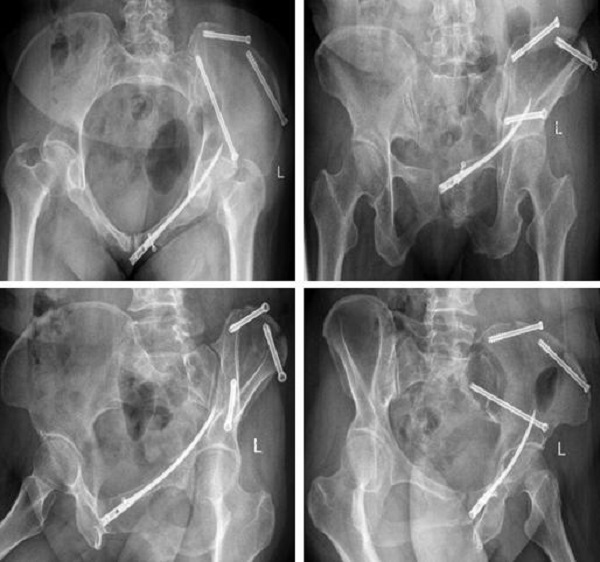

术后复查: